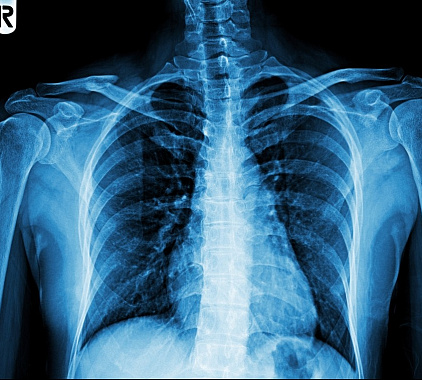

Расшифровка результатов

После рентгенографии лопатки начинается анализ готовых результатов. Врач просматривает изображения. Сравнивает значения с нормой. В своем протоколе специалист указывает характеристики костей, суставных сочленений, соседних элементов. Он отражает выявленные патологии. Пишет выводы.

В норме на рентгене:

- форма лопатки обычная, расположение типичное;

- структура и контуры костей без изменений;

- травмы и деструктивные процессы не определяются;

- опухоли и воспаления отсутствуют.

Полученный отчет и рентгенограммы следует передать лечащему доктору. Врач поставит диагноз. Он расскажет о необходимом лечении. Огласит прогноз.